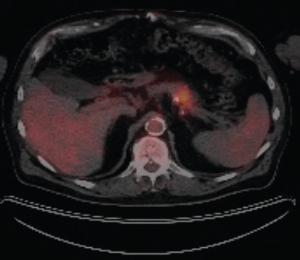

ABSTRACT Gastrointestinal stromal tumors (GISTs) are rare neoplasms of the gastrointestinal tract. They commonly present with nonspecific symptoms and thus are often discovered incidentally. They are best identified by CT scan and most stain positive for CD117 (C-Kit), CD34, and/or DOG-1. Several risk stratification classification systems have been developed based on tumor size, mitotic rate, location, and perforation. Traditional chemotherapy and radiation therapy have been very ineffective, making surgery the mainstay of treatment. The discovery of mutations associated with these tumors has revolutionized the treatment approach. Imatinib mesylate, a selective tyrosine kinase receptor inhibitor, used as adjuvant or neoadjuvant therapy, has greatly improved the morbidity and mortality associated with GISTs. As the survival of patients has increased with the long-term use of targeted therapies, quality-of-life issues now have become much more relevant and have come to the forefront of care. We present a young woman who was successfully treated for GIST but now faces associated long-term adverse effects of imatinib, including the challenge of preserving fertility and the potential for childbearing.